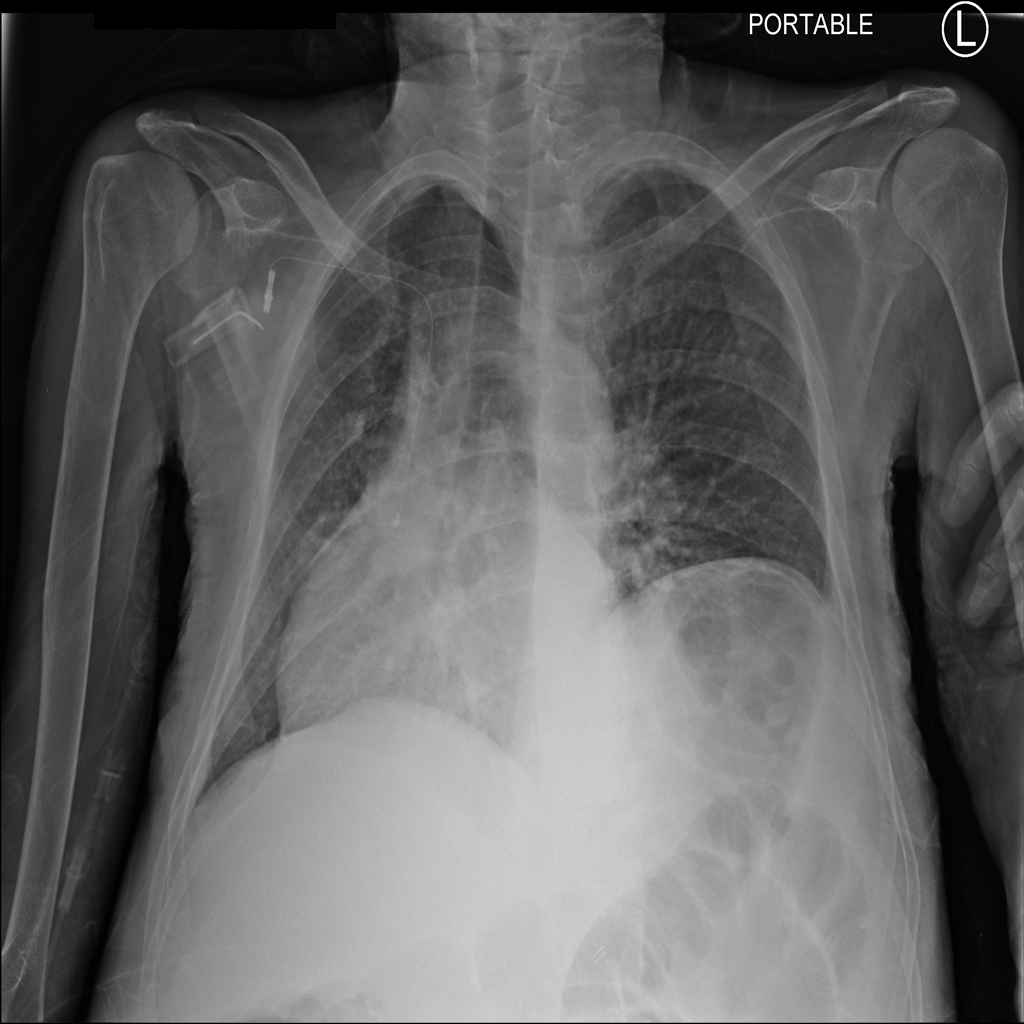

PAT-3384 · IMG-000Cardiomegaly

PAT-3384 · IMG-000

AP